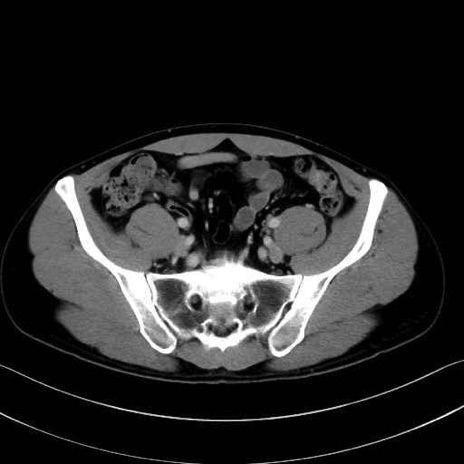

3. 殿部の筋肉(表層・中層・深層)

大殿筋 (Gluteus maximus)

中殿筋 (Gluteus medius)

小殿筋 (Gluteus minimus)

大腿筋膜張筋 (Tensor fasciae latae)

5. 大腿前面(大腿四頭筋群・伸筋群)

縫工筋 (Sartorius)

大腿直筋 (Rectus femoris)

外側広筋 (Vastus lateralis)

中間広筋 (Vastus intermedius)

6. 大腿内側(内転筋群)

恥骨筋 (Pectineus)

長内転筋 (Adductor longus)

短内転筋 (Adductor brevis)

大内転筋・小内転筋 (Adductor magnus / Adductor minimus)